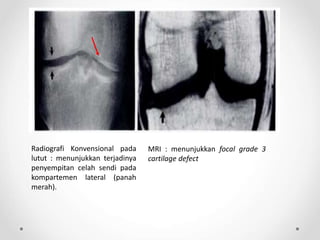

Radiografi Konvensional pada

lutut : menunjukkan terjadinya

penyempitan celah sendi pada

kompartemen lateral (panah

merah).

MRI : menunjukkan focal grade 3

cartilage defect

Radiografi Konvensional pada lutut: menunjukkan terjadinya penyempitan celah sendi pada kompartemen lateral (panah merah). MRI : menunjukkan focal grade 3 cartilage defect